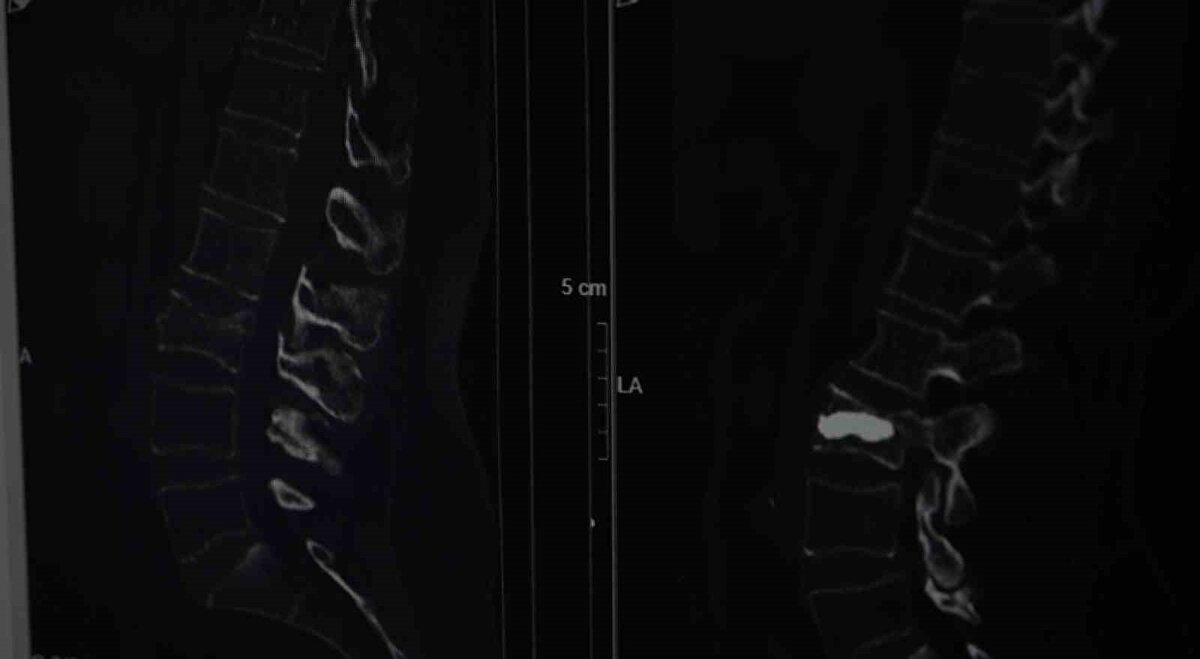

Burada Beyin ve Sinir Cerrahisi Uzmanı Doç. Dr. Şevket Evran ve ekibinin yaptığı incelemelerde kemik erimesine bağlı kırık tespit edildi. Armağan, durumu şaşkınlıkla karşılarken doktorlar operasyon gerekliliğini ifade etti. Genellikle kemik erimesine bağlı omurga kırıklarını tedavi etmek amacıyla uygulanan minimal invaziv bir cerrahi yöntem olan ve hastanın aynı gün normal yaşamına dönebilme imkanı sunan kifoplasti operasyonu 25 Ağustos günü gerçekleştirildi. Doç. Dr. Evran ve ekibinin yaptığı operasyon başarılı geçerken Armağan da rahat bir nefes aldı. Doç. Dr. Evran, özellikle menopoz sonrası kadınlarda kemik erimesi kaynaklı oluşan kırıklarına dikkat çekerken tedavilerine ilişkin bilgi verdi, vatandaşlara önemli uyarılarda bulundu.

Yaşadıklarını anlatan 76 yaşındaki Alis Armağan, "Bahçe kapısının önünde düştüm, ne olduğumu anlayamadım. Hiçbir yerimde ne çizik ne morartı var, öyle bir düşme. Herhalde 2 tane fıtığım var, düşmeyle onlar yine nüksetti dedim. İğneler oldum, geçmeyince bu başka bir şey diyerek doktora müracaat ettik. Hemen de ayaklandım, Allah’a şükür, her gün doktoruma dua ediyorum. Allah kimseye böyle sıkıntılar vermesin, hele ileri yaş için çok zor. Düşmem ağustos başıydı, ameliyat 25 Ağustos’ta oldu, fıtık filan diyerek oyalandım. Sonra MR çekildik, tespit edildi. Yoksa ameliyat öncesi perişandım. Bu yaştan sonra ameliyat mı olur dedim, herkes de yaşlılar çok zor, çok riskli diyor. Hastaneye çok umutsuz geldim ama iyi çıktım" diye konuştu.

"Omurga kırıklarını menopoz sonrası bayanlarda sıklıkla görüyoruz" diyerek sözlerine başlayan Doç. Dr. Evran, "Bu hastalarda travma sonrası kemik yoğunlukları düşük olduğu için omurgalarında kırık oluşma ihtimali normal popülasyona göre çok daha fazla görülüyor. Travma geçiren menopoz sonrası bir insanda kemik yoğunluğuna daha önce dikkat etmemiş, bununla ilgili daha önce tedavi almamışsa bu hastalarda travma sonrası oluşan, bel, sırt, boyun ağrılarında özellikle bu kırıklar düşünülmekte. Bir beyin ve sinir cerrahisi hekimine başvurmaları önerilmekte. Vücudun daha çok yük taşıyan bel ve sırt bölgelerinde oluşuyor. Hasta sırt veya bel ağrısıyla travma sonrası başvurduğu zaman önce gerekli tetkiklerini yapıyoruz. Görüntülemelerinde kırığı tespit etmiş olursak ve bu bir travma sonrası gelişen bir kırıksa bu kırıkta öncelikle omurgadaki çökme miktarının derecelerine bakıyoruz. Derecelere göre korse, yatak istirahati gibi tedavileri öncelikle deniyoruz. Fakat kırığın çökme derecesi çok ileriyse veya omuriliğe bir zarar söz konuysa daha minimal invaziv olarak tedaviler ve daha ileri hastalarda cerrahilerle omurgaya enstrümantasyonlarla tedavi edebiliyoruz" dedi.

Tedavi seçeneklerine yönelik konuşan Doç. Dr. Evran, "Hastanın klinik durumu uygunsa vertebroplasti veya kifoplasti dediğimiz halk arasında omurgaya çimento doldurma olarak bilinen işlemi bu hasta grubunda uygulamak öncelikli tercihimiz oluyor. İşlemin bazı avantajları var; eskiden bu tarz kırıklarda hastaları günlerce yatakta yatırıp hatta tüm vücut alçıya alınıp tedavi edilirmiş ama günümüzde teknolojinin de ilerlemesiyle artık bu yöntemler daha ön planda. Vertebroplastide hastanın cildinde büyük bir kesi olmadan sadece bir iğnenin geçtiği kadar bir delikten iğne yardımıyla girilerek omurganın içine bazen tek bazen çift taraflı girilerek başlangıçta içinde sıvı olan sonra katılaşan bir maddeyi enjekte ediyoruz. Omuriliğin içinde donuyor. Başka bir yöntemi olarak da bazen omurganın içinde bir balon yardımıyla balon şişirerek omurganın eski yüksekliğini kazanmasına ve daha güvenli bir alan oluşturarak balonun şiştiği alana çimento dediğimiz şeyle doldurarak hastanın da ağrılarının geçmesini sağlamış oluyoruz, akşamına hasta taburcu edilebiliyor" diye konuştu.

Sözlerini sürdüren Doç. Dr. Evran, "Bu tarz hastalar kliniğimize çok başvuruyor sadece kliniğimize değil Türkiye hatta dünya genelinde bu tarz hastalar çok fazla. Bu cerrahiyi uyguladığımız ayda ortalama 4 ila 5 hasta. Bu hastamızda bir travma sonrası bel omurgasında kırık meydana gelmiş, ilk planda kırık olarak algılamıyor, şiddetli ağrılardan vücudunda kötü bir şey geliştiği yönünde bir kanaate varmış. Ameliyat sonrası 4’üncü saat, ayağa kalkarak yürümesini sağladık. Osteoporoz olan hastalarda omurga kırıklarını önlemenin yollarından bir tanesi de menopoz sonrası bayanların mutlaka kemik yoğunluğuna baktırması gerekiyor. Hastalar bu tarz travmalardan sonra ağrılarını birçok şeye yorabiliyor. Özellikle bel fıtığı, belinde kas güçsüzlüğü, düzleşme gibi hastamız da önce bel fıtığından şüphelenerek ağrılarının ona bağlı olduğunu düşünmüş fakat dirençli bir ağrı. Hiçbir medikal tedavi, ilaçla ağrıları dinmeyince durumun daha farklı boyutta olduğunu düşününce hastanemize başvurmuş" dedi.